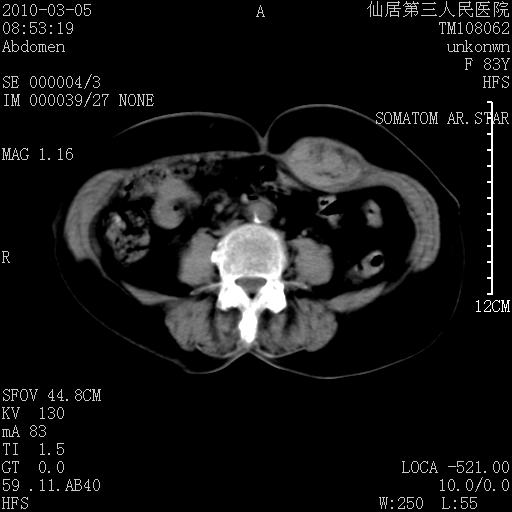

标题: CT24879:腹直肌病变。在线等。

女性,83y,腹痛一周。

考虑:左侧腹直肌神经纤维瘤可能

神经纤维瘤—伴有出血?

有无外伤,血肿或韧带样瘤